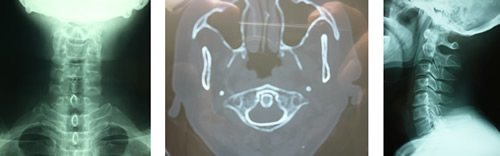

頸部に回旋する時に起こる上部頸椎と後頭骨に痛みを感じ又、同側の舌の半分がしびれ舌の違和感を感じたり頭痛の原因にもなります。急に頸椎を回旋すると頸椎2番目が環軸関節上でけん引され大後頭神経、小後頭神経に影響を与え、頭痛、舌の違和感の原因にもなるといわれています。私の調査研究では軽い環軸関節(後頭骨と第一頸椎)の歪みは多数の患者さんに見受けられました。又、歪みは椎骨動脈の歪みにもなり血流の変化に関与します。

又、頸部交感神経に影響を与え頭痛、目、鼻、喉頭、耳まで様々な症状を呈するのではないかと思われます。